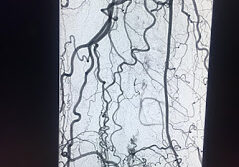

Popliteal Artery chronic total occlusion in the patient with CLI